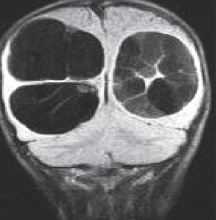

Нейроглиальные (нейроэпителиальные) кисты - врождённые кисты различной этиологии, локализующиеся в паренхиме мозга или в области сосудистого сплетения желудочков. Обычно округлые, с гладкими стенками. Очень часто такие кисты сочетаются с аномалиями развития: отсутствием прозрачной перегородки и полимикрогирией. При МРТ головного мозга содержимое кист ликворное, иногда с небольшой примесью белка.

Кисты средней линии - киста прозрачной перегородки (cavum septi pellucidi), полость Верге (cavum Vergae) и киста промежуточного паруса (cavum veli interpositi) - являются нормальными структурами головного мозга плода. В течение 6 месяцев после рождения у большинства людей они запустевают, но могут и сохраниться, визуализируясь при этом на МРТ головного мозга. По-видимому, эти полости не имеют клинического значения и относятся к случайным находкам при томографии. Киста прозрачной перегородки (еще называют V желудочком) является медиальной стенкой боковых желудочков и ограничена спереди коленом мозолистого тела, сверху мозолистым телом и сзади столбами свода . Полость Верге представляет собой продолжение кисты прозрачной перегородки кзади и расположена между телами желудочков . Обычно обе кисты сочетаются. Киста промежуточного паруса расположена в крыше III желудочка (tela choroidea), между треугольниками боковых желудочков на уровне отверстий Монро. Она ограничена сверху мозолистым телом, cзади цистерной четверохолмия и снизу III желудочком.